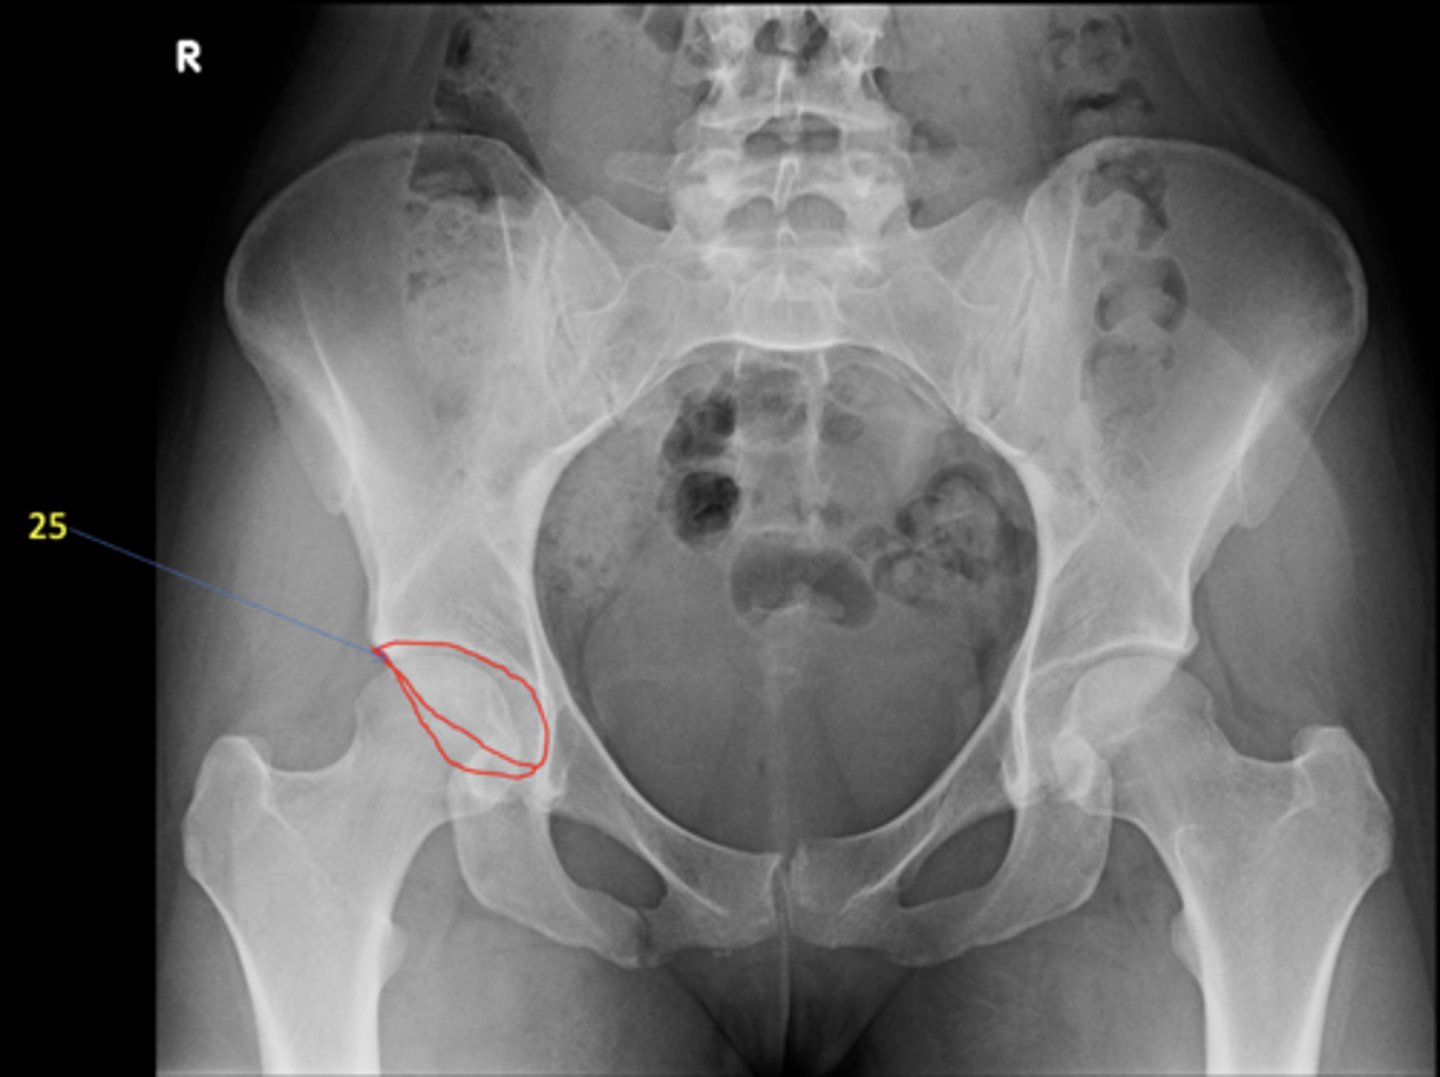

1

New cards

AP pelvis

View?

<p>View?</p>

22

Right acetabulum

ID 25

<p>ID 25</p>

25

Right ischial tuberosity

ID 28

<p>ID 28</p>